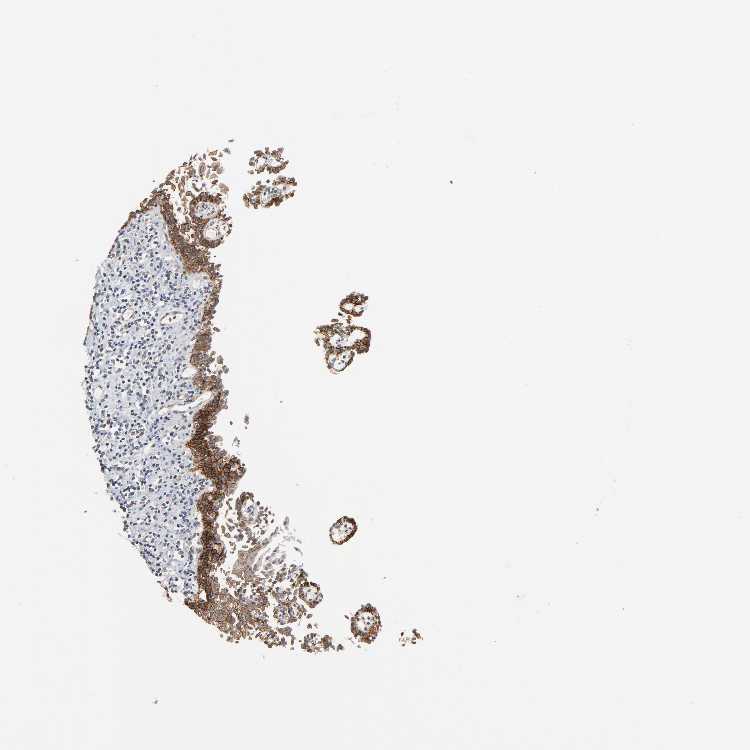

ESOPHAGUS - Antibody stainingi

Antibody staining in the annotated cell types in the current human tissue is reported as not detected, low, medium, or high, based on conventional immunohistochemistry profiling in selected tissues. This score is based on the combination of the staining intensity and fraction of stained cells.

Each image is clickable and will lead to virtual microscopy that enables deeper exploration of all samples and also displays staining intensity scores, fraction scores and subcellular localization as well as patient and tissue information for each sample.

Antibody HPA004931

Squamous epithelial cells Medium